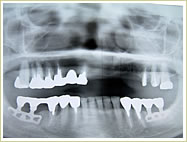

症例 54歳 男性 インプラント埋入数:11本 画像拡大

治療前 治療後